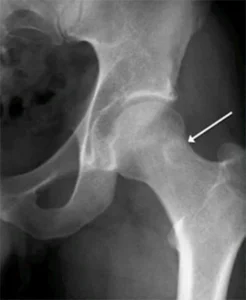

🔹 Lesioni a livello dell’anca

- Possono generare dolore riferito, spesso confuso con quello causato da una compressione della radice nervosa dovuta a ernia del disco.